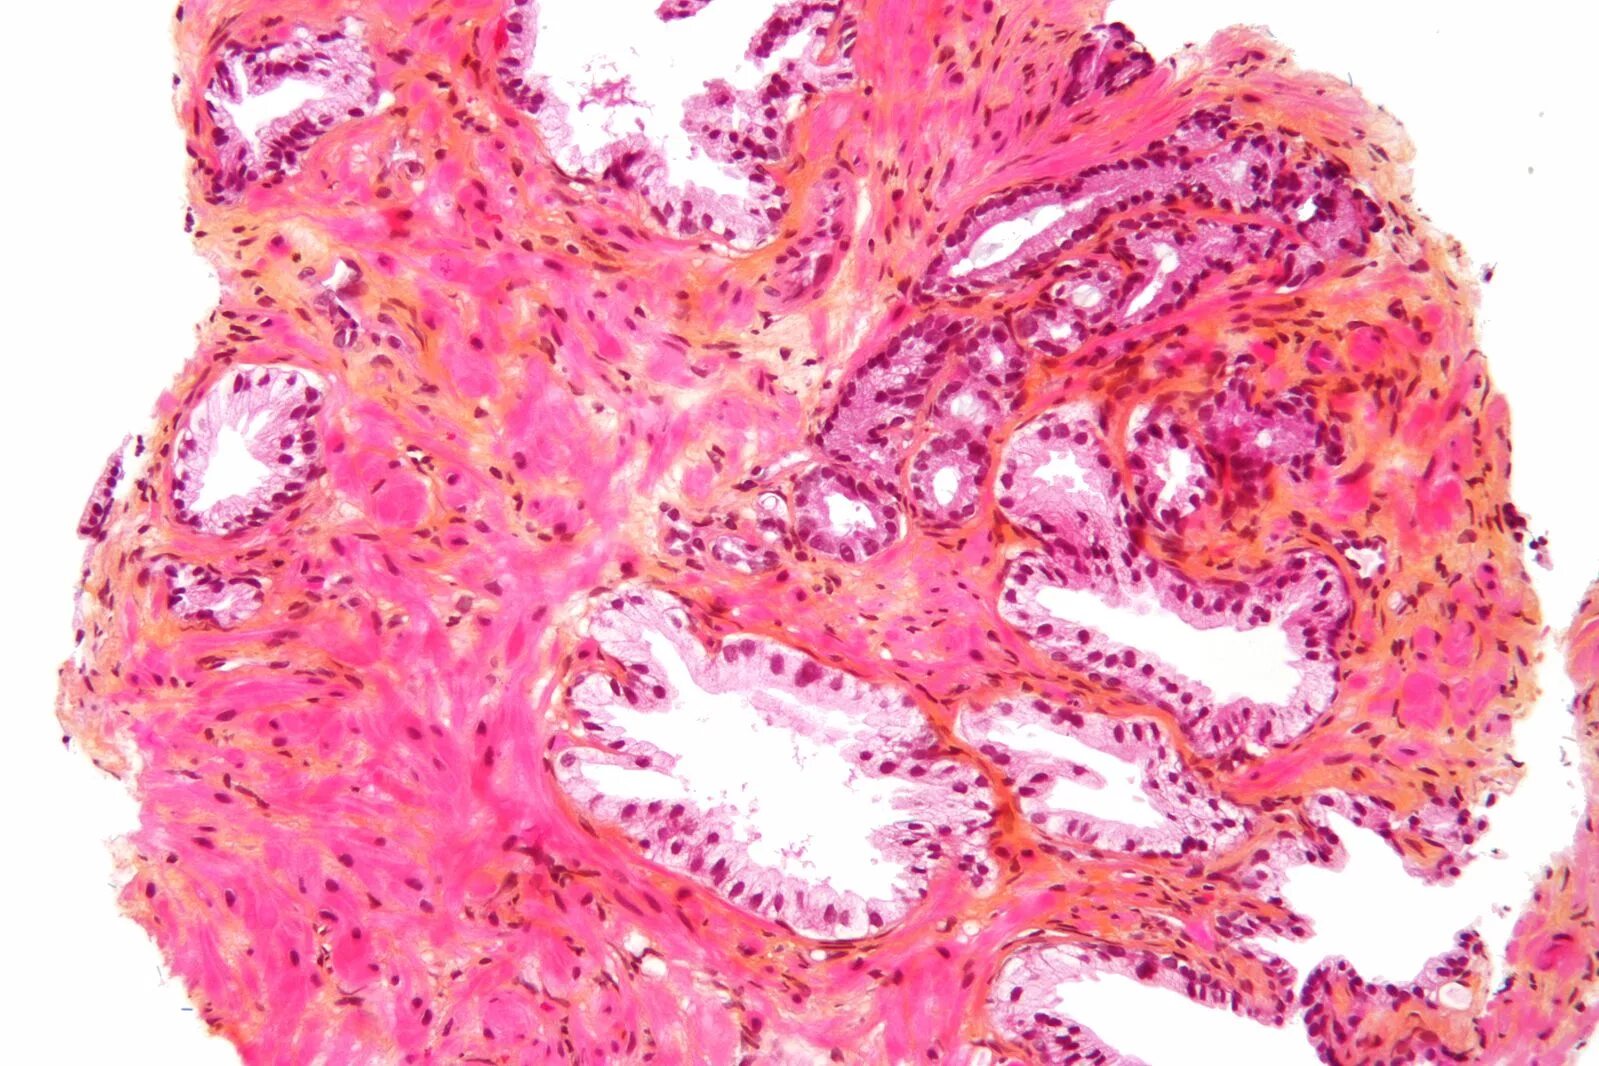

Срочные гистологические исследования